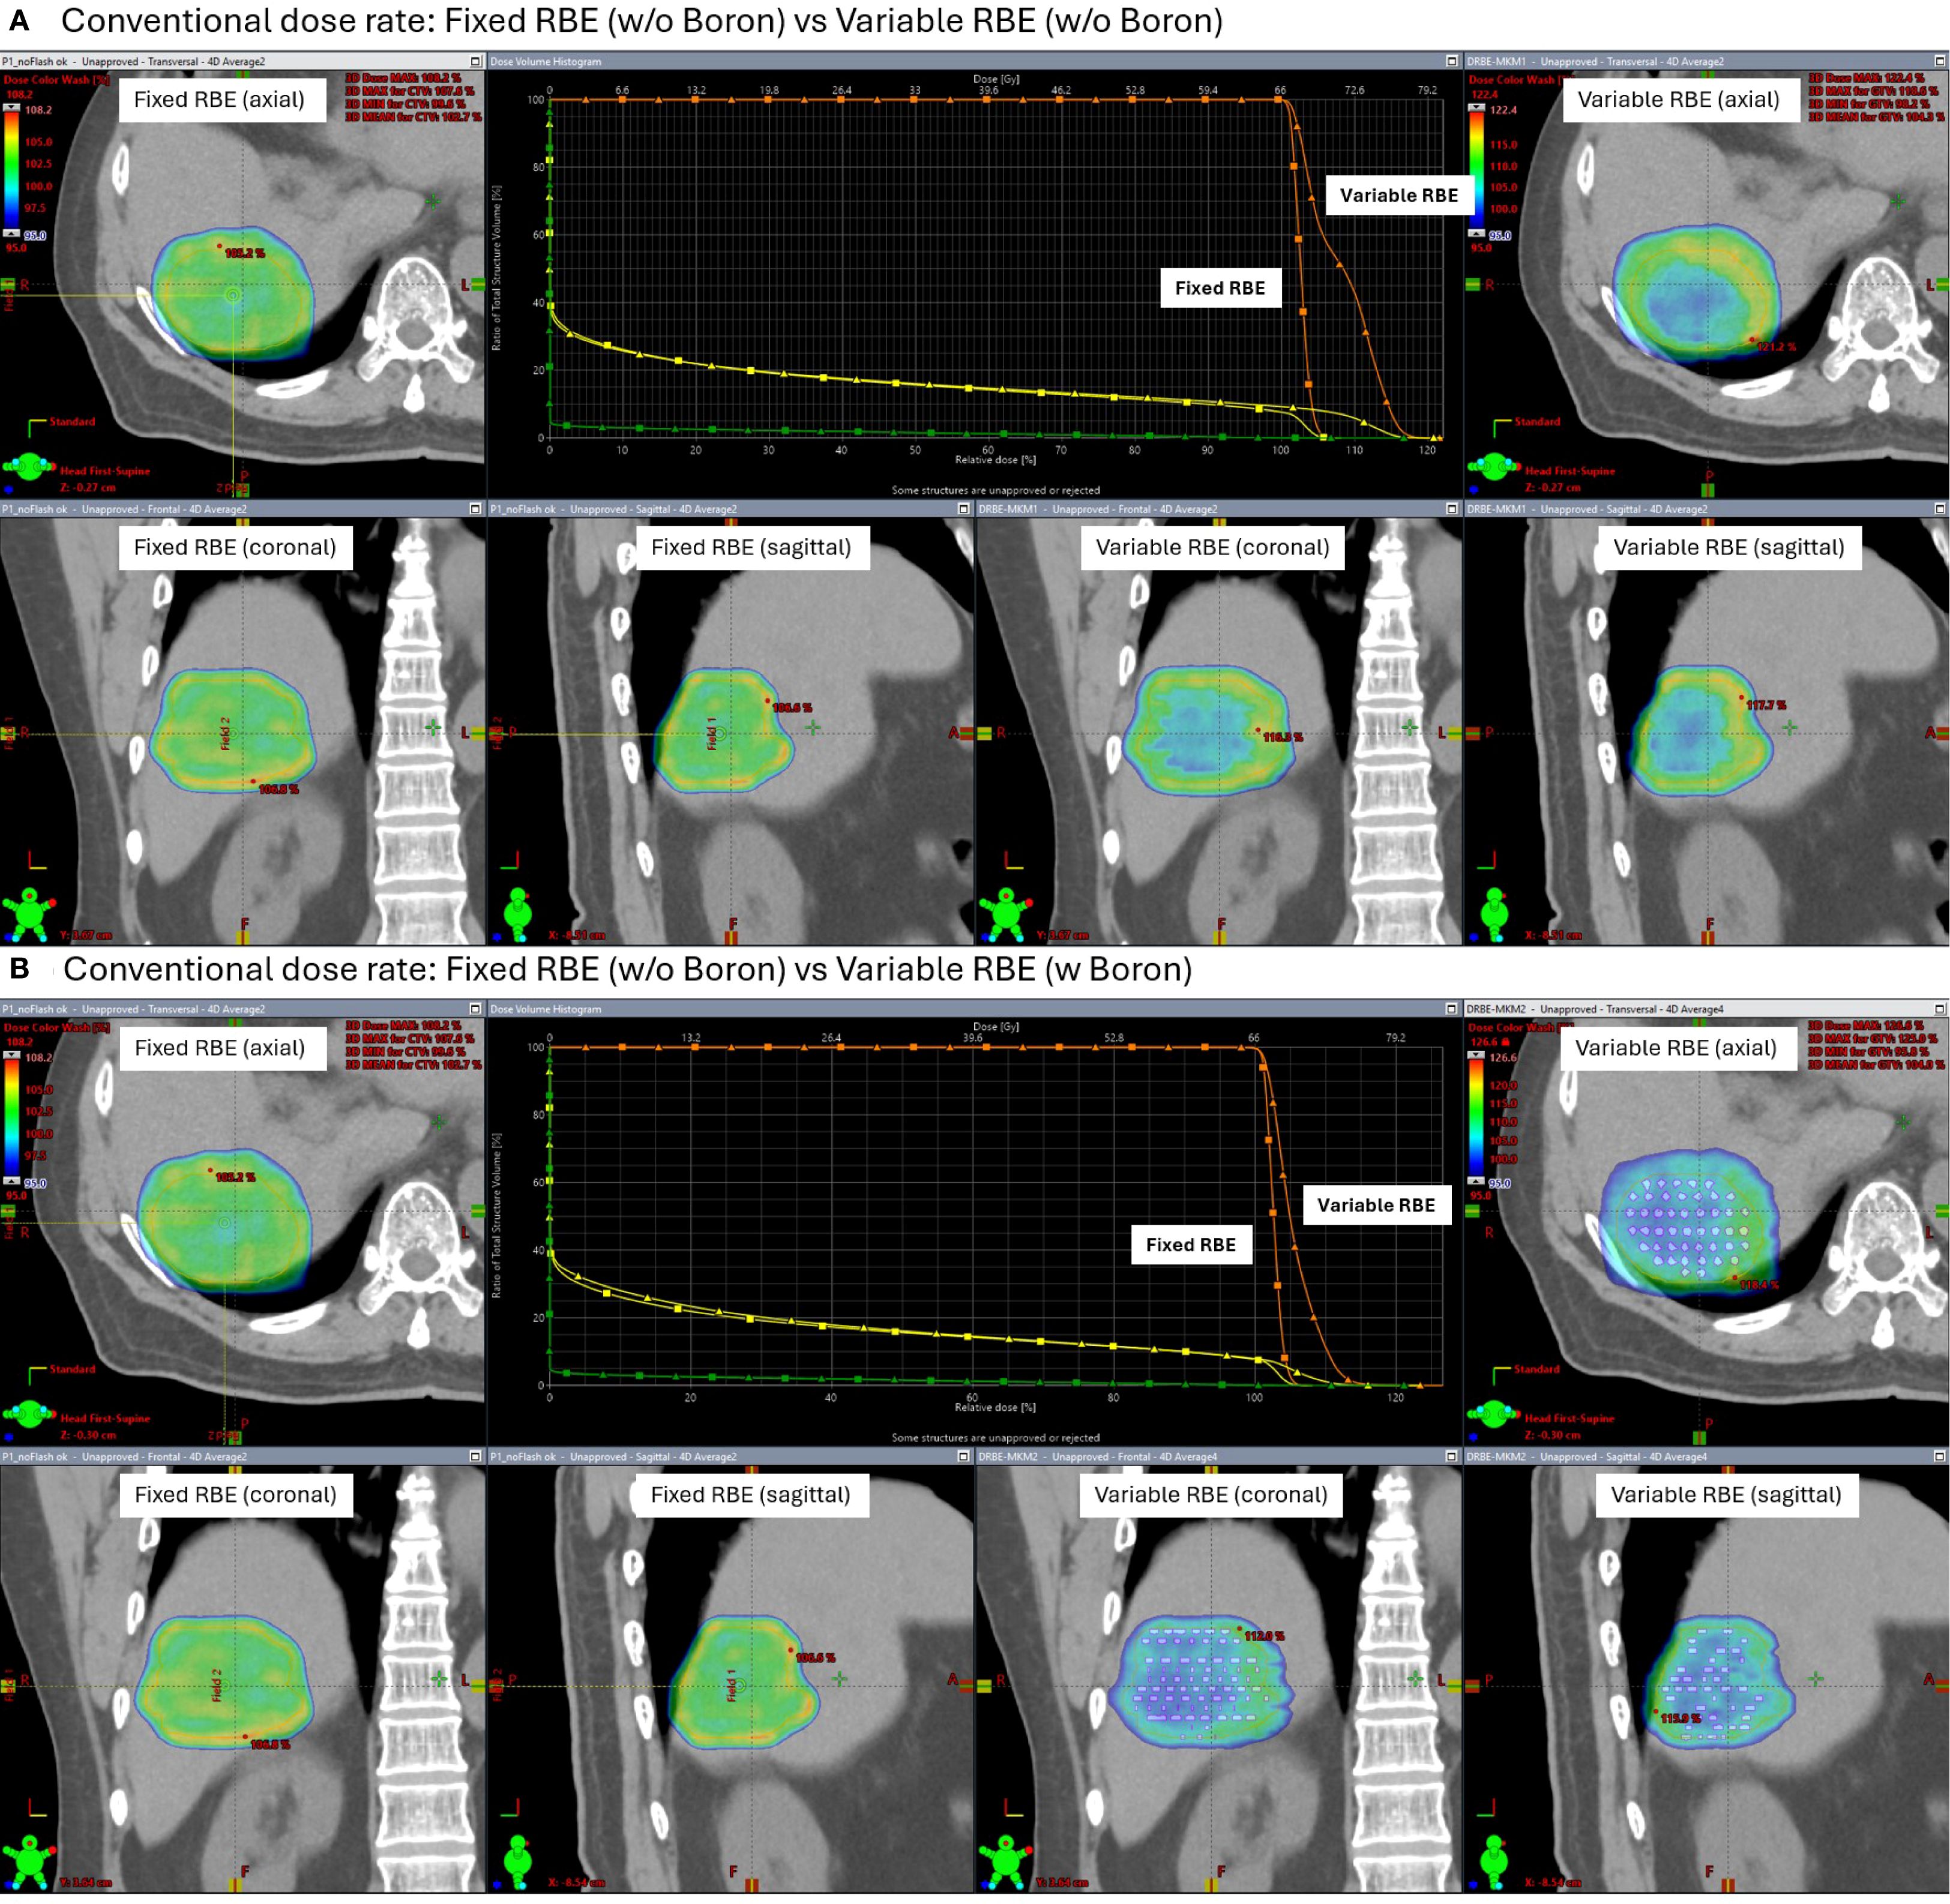

Figures 7 and 8 show the dose distributions and dose volume histogram (DVH) across the CTV under conventional and FLASH dose-rate conditions, respectively. Each figure includes comparisons between fixed and variable RBE dose calculations, with and without the high-density insert. Under conventional dose rates (Figure 7), the variable RBE plan without the insert exhibited dose heterogeneity due to LET variation. When the high-density insert was included, dose uniformity in the CTV improved, indicating that localized changes in stopping power can affect LET-weighted biological dose.

Figure 7

Medical imaging comparison panels showing dose distribution for fixed and variable relative biological effectiveness (RBE) in the context of boron presence. Panel A (top) compares fixed and variable RBE without boron, including axial, coronal, and sagittal views with a dose-response graph. Panel B (bottom) repeats the comparison but with boron, showing similar view orientations and another graph. Brightly colored overlays indicate dose regions within the scans.Figure 7. Simulated dose distributions and Dose Volume Histogram (DVH) under conventional proton therapy. Comparisons are shown between fixed and variable relative biological effectiveness (RBE) models, both without (A) and with (B) a high-density boron insert (2.34 g/cm³) placed in the CTV.

Under FLASH dose-rate conditions (Figure 8), the difference between fixed and variable RBE distributions was reduced even without the insert suggesting that FLASH delivery may inherently mitigate LET-driven dose variations. When the high-density region was added under FLASH, further improvement in dose homogeneity was observed, reinforcing the idea that both dose rate and local stopping power changes can influence biological dose shaping.